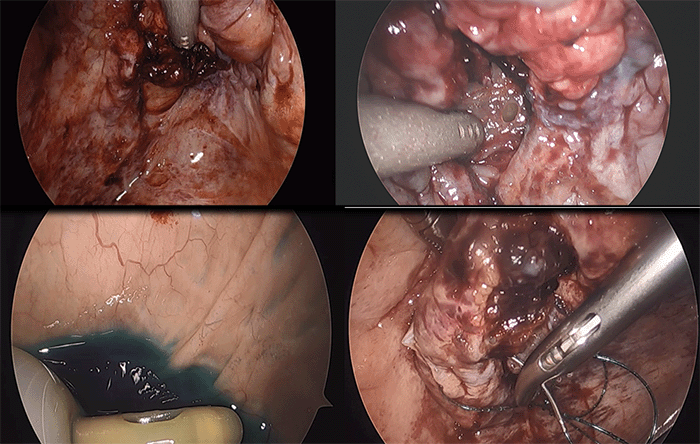

On postoperative day 16, the patient presented to the emergency department complaining of abdominal distension, nausea, vomiting, and inability to urinate for the past two days. He reported no trauma at home and his vital signs were within normal range. Physical examination revealed diffuse abdominal tenderness and guarding. Laboratory results showed elevated creatinine (11.03 mEq/L), WBC count (13,500/mL), and a CMV IgM level <30 U/mL. Notably, the patient had not undergone a dedicated bladder scan since discharge, despite experiencing delayed graft function (DGF) and oliguria. Upon admission, a CT abdomen and pelvis (CTAP) without IV contrast revealed a significant amount of free fluid in the abdomen (Figure 1), leading to a presumptive diagnosis of peritonitis secondary to a urinary leak.

Figure 1. CT Scan on Admission Showing Free Intraperitoneal Fluid. Published with Permission

The kidney transplant graft, ureteral stent, and bladder can be appreciated. The arrow indicates where the bladder perforation was found; in retrospect, a clot was in that area (found during laparoscopy).